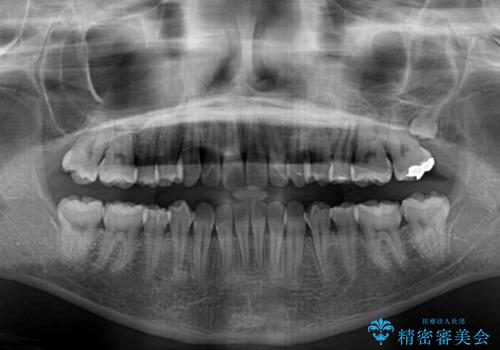

- 上の前歯、および下の歯列全体のでこぼこを気にして来院された患者様です。

インビザラインを用い、IPR(歯と歯の間を削る)と歯列全体を後方に移動させることで、歯並びを整えていくこととしました。

歯列全体を後方に移動させるため、下顎の親知らず2本を抜歯することとしました。